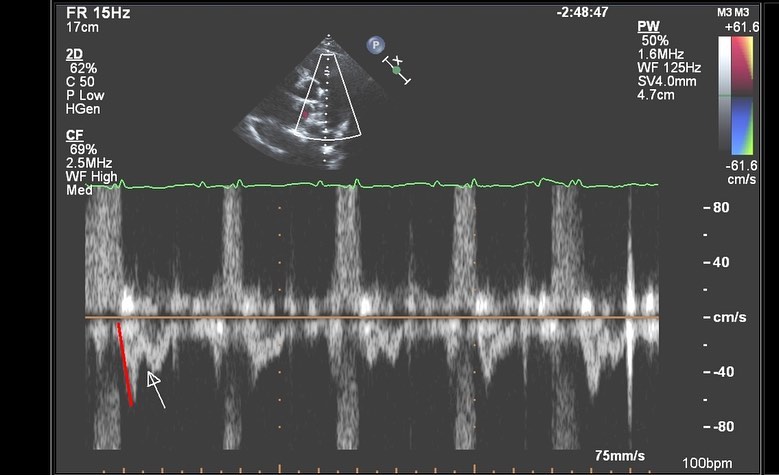

📷3️⃣: This pulsed wave Doppler shows several important features consistent with PHT. First the RVOT VTI is notched (white arrow), quite abnormal due to reflected waves that return during RV systole. Also note the steep acceleration time to peak velocity (red line), 60ms in this individual (<80ms in this context goes along with high PA pressures).